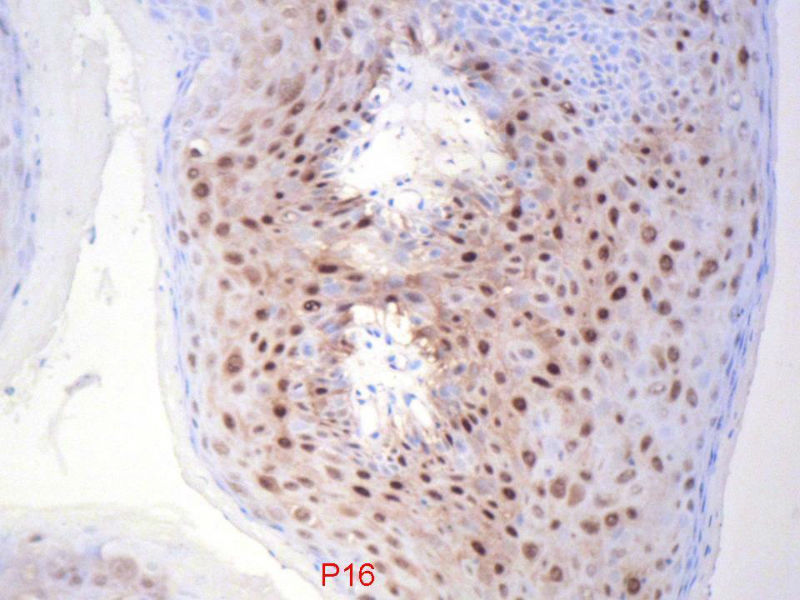

男,72岁,右耳听力下降两个月,检查右外耳道有黄豆大肿物,表面乳头状,手术切除。

您看了这样的免疫组化结果,会有什么样的考虑呢?